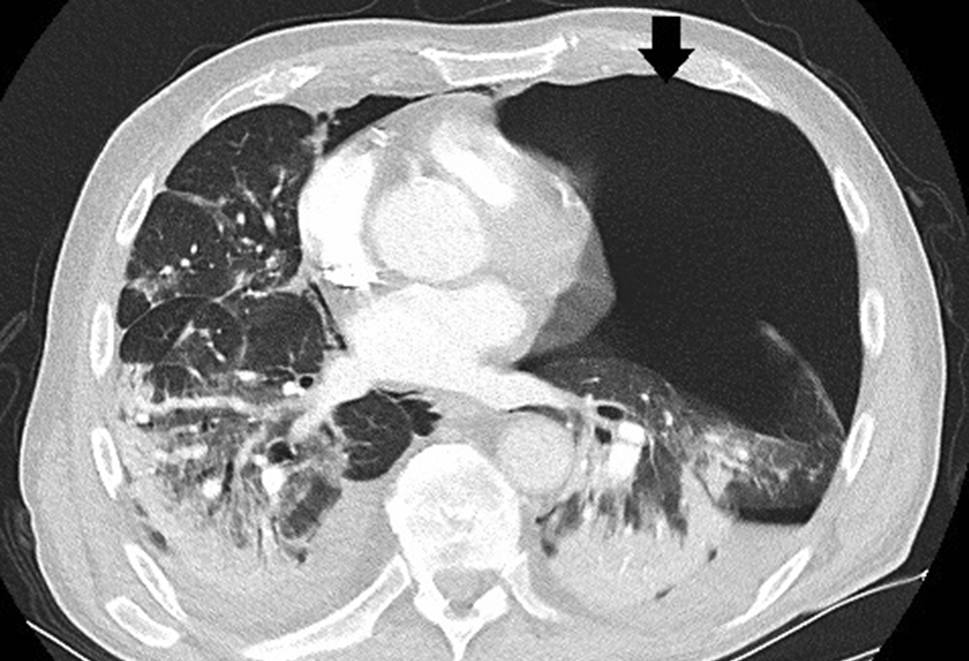

Das Thorax-CT am Aufnahmetag zeigte bilaterale milchglasartige Verschattungen. Antibiose mit Piperacillin/Tazobactam wurde eingeleitet. Unter High-flow-Sauerstofftherapie stabilisierte sich die O2-Sättigung bei 92 %. Am Tag 9 entstand eine respiratorische Dekompensation. Nach Stoßtherapie mit 1 g Methylprednisolon über 4 Tage und anschießender Gabe von Prednisolon 50 mg täglich sowie Masken-CPAP-Atmung stabilisierte sich die respiratorische Situation. Das Kontroll-Thorax-CT zeigte Zunahme der Infiltrate, ein Pneumomediastinum und einen minimalen linksseitigen Pneumothorax (Abb. 3). Eine linksseitige Thoraxdrainage wurde gelegt. Am Tag 14 entstand rapide eine respiratorische Globalinsuffizienz, sodass Intubation und in weiterer Folge die Anlage eines Tracheostomas erforderlich wurden.

Abb. 3

Pneumomediastinum (Pfeil), schmaler Pneumothorax (2 Pfeile)

Trotz expandierter Lunge und Regredienz des Mediastinalemphysems persistierten Decarboxylierungs- (pCO2 55–95 mm Hg) und Oxygenierungsprobleme (OI 90–120). Bei liegender Thoraxdrainage entwickelte sich 5 Tage später ein neuerlicher, apikal gekammerter Pneumothorax (Abb. 4), der gezielt mit einer weiteren Drainage versorgt wurde. Nach 16 Tagen Beatmung über den Tubus („dual positive airway pressure“, Spitzendrücke 30 mbar, durchschnittlicher „driving pressure“ 18 mbar) ohne eindeutige Besserungstendenz der respiratorischen Situation und bei weiterer Verschlechterung der Hämodynamik trotz kontinuierlich steigender Katecholamindosen verstarb der Patient am Tag 31 der intensivmedizinischen Behandlung an einer abdominellen Blutungskomplikation.

Abb. 4

Pneumothorax (Pfeil) trotz liegender Thoraxdrainage (Stern). Das diskrete Weichteilemphysem in den Mm. pectorales beidseits ist in diesem Fall Folge der Tracheostomie